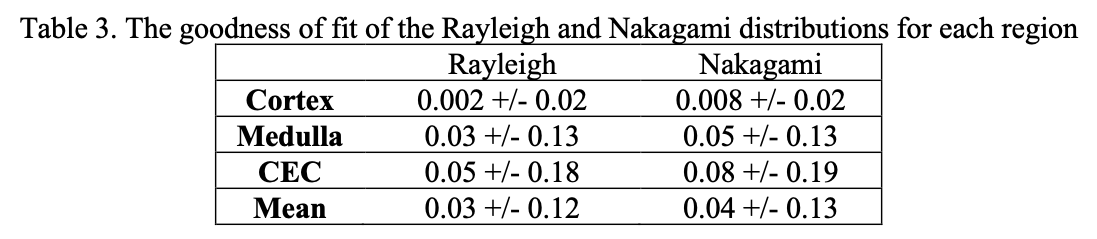

Table 1 summarizes the parameters and if they were significantly different between regions. Only two distributions, Nakagami and Rayleigh, had parameters that achieved significant differences in all three regions. These two distributions were the only ones used for subsequent KL divergence and goodness of fit analysis. Table 2 summarizes the divergence values.

Given the higher divergence values, the Nakagami distribution captures the distinctiveness of each region in a compelling manner. In comparing the cortex and medulla for example, two regions which are visually close together in echogenicity and difficult to segment, the Nakagami distribution has higher divergences compared to the Rayleigh distribution. Table 3 summarizes the goodness of fit for these distributions.

We observe low fitting error in both distributions, with no significant differences in the sum of squares error for either one. While both Rayleigh and Nakagami distributions have excellent model fitting and divergence values, the Nakagami can be used in a more general manner than the Rayleigh. The Nakagami shape parameter, m, can be used to determined pre-Rayleigh, Rayleigh, and post-Rayleigh scattering conditions. We select this distribution for stratification.